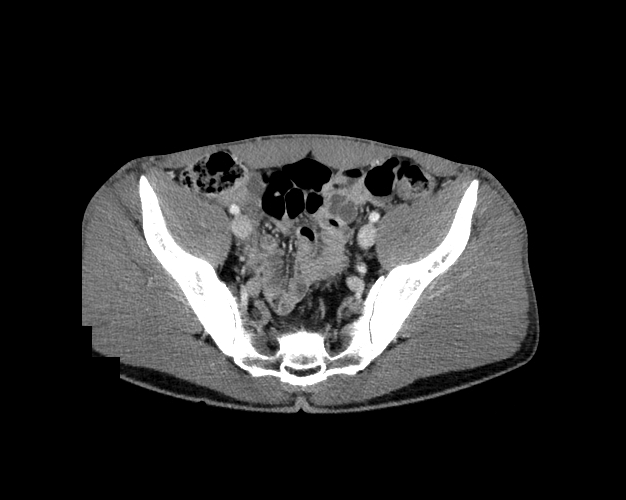

Pelvis

Covers pelvic MRI anatomy.